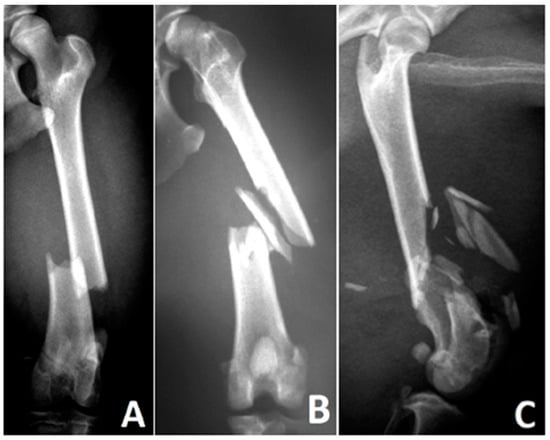

Fractures were characterized and classified following the system by Unger et al. [6]. In addition, the number and size of bone fragments were counted and visually categorized relative to the bone diameter (Figure 1A):

-

Small fragments: Maximum dimension less than one-third of the bone diameter.

Medium fragments: Greater than one-third but less than two-thirds of the bone diameter.

Large fragments: Greater than two-thirds of the bone diameter.

The comminuted zone was defined as the area between the two main fragments before surgical reduction (Figure 1B):

The proximal boundary of the comminuted zone was the most distal intact bone cross-section of the proximal fragment.

The distal boundary was the most proximal intact bone cross-section of the distal fragment.

The boundaries are orthogonal to the bone’s longitudinal axis. The bone diameter was defined as the average of the two bone cross-sectional areas that limit the comminuted zone. For paired bones, only the radius and tibia were considered.

The extent of the comminuted zone was measured radiologically along the bone’s longitudinal axis, compared to the bone diameter, and expressed as a percentage (e.g., 50% means the extent of the comminuted zone is equal to half the bone’s diameter).

Figure 1. (A): Left femur of a 5-year-old female Collie—small (*), medium (°), and large (#) fragments. (B): Proximal (a) and distal (b) boundaries of the fragment zone (c) using an example of a canine tibia.